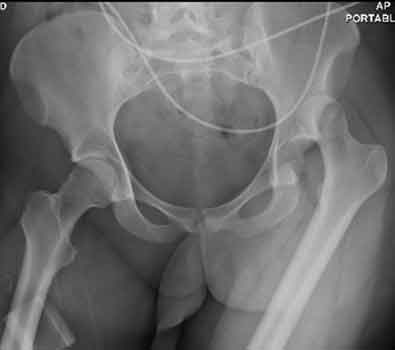

Posterior hip dislocation.

23) What abnormalities of the pelvis can be observed in the image below?

In the above image the sacroiliac joint and the ipsilateral ischiopubic rami are fractured, making the answer to the question "All of the Above."

24) Based on your findings, name the condition shown in the image above. Malgaigne Fracture